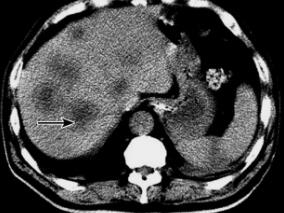

1小时条评论以下列举四类笔者收治的罕见腹膜后肿瘤个案,希望以点代面,经验交流和总结。 (一)罕见的腹膜后促纤维增生性小圆细胞瘤个案 患儿:女,5岁。因阵发性腹痛3个月,加重2天,发现腹部包块1天入院。3个月前出现无明显诱因腹痛,当地对症治疗后缓解,未进一步检查。此...